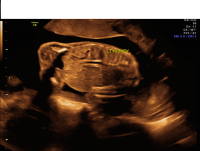

Unilateral renal agenesis coronal

After birth, special imaging will be performed to confirm the prenatal diagnosis. Unfortunately, many cases with bilateral renal agenesis will not survive the pregnancy, and those that do will pass away shortly after birth. Unilateral renal agenesis, on the other hand, is associated with an excellent outcome. Unilateral renal agenesis is often asymptomatic and associated with a normal lifespan.